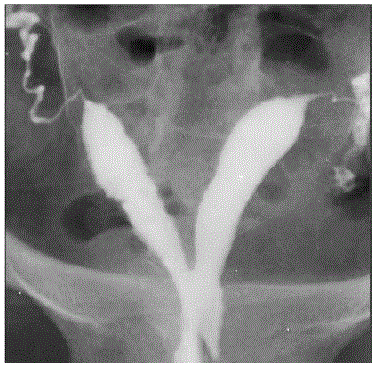

Veja a imagem abaixo e marque o diagnóstico.

Créditos:

https://www.google.com.br/search?q=hidrossalpinge+bilateral&source=lnms&tbm=isch&sa=X&ved=0ahUKEwj0_OioqbHaAhUBk5AKHWEzAksQ_AUICigB&biw=1024&bih=662#imgrc=a6s-NHneRkhrCM: